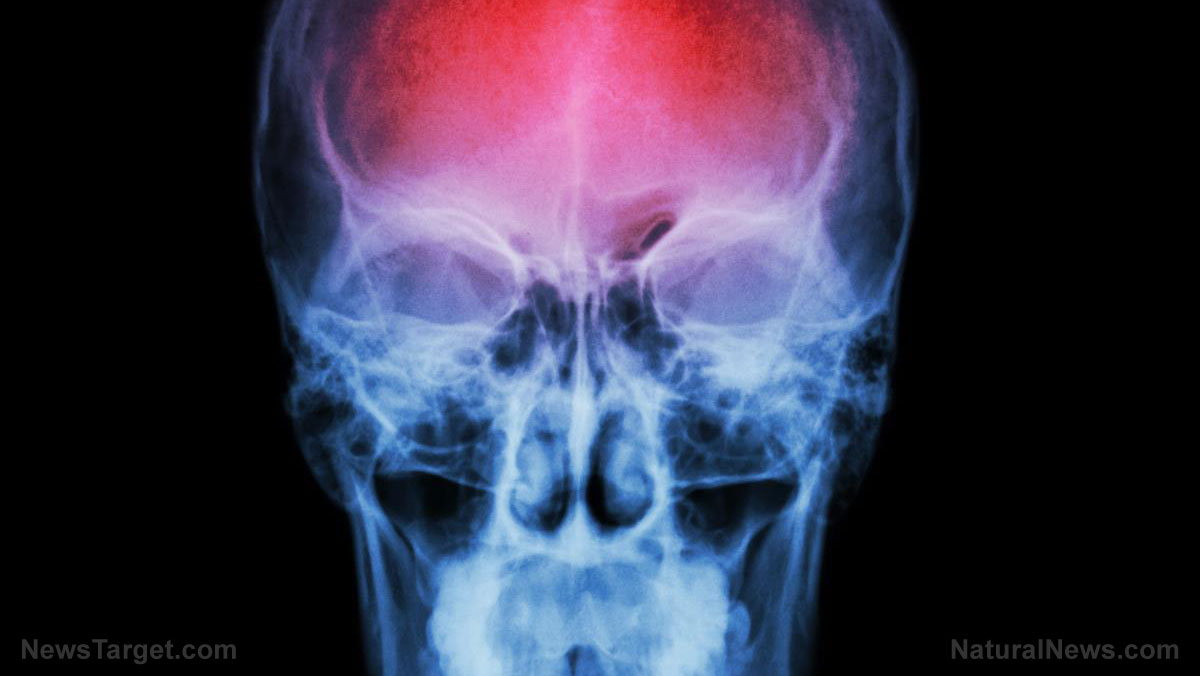

A shocking new peer-reviewed study has exposed the lingering dangers of mRNA COVID-19 vaccines, revealing that spike protein—the toxic byproduct of Pfizer and Moderna’s experimental shots—was found in the brains of stroke victims up to 17 months after vaccination. Published in the Journal of Clinical Neuroscience, the research examined 19 hemorrhagic stroke cases from 2023 and 2024, discovering that 43.8% of victims still had vaccine-derived spike protein lodged in their cerebral arteries—all of them women.

The study, conducted by 10 Japanese researchers, found that in three patients, spike protein remained detectable 11, 12, and 17 months after vaccination—long after Big Pharma and government health agencies assured the public it would be gone.

Dr. Plothe stated: “While the study does not definitively prove causation, the detection of spike protein in brain arteries—combined with signs of immune cell infiltration—suggest a plausible mechanism for blood vessel damage and hemorrhagic strokes.”